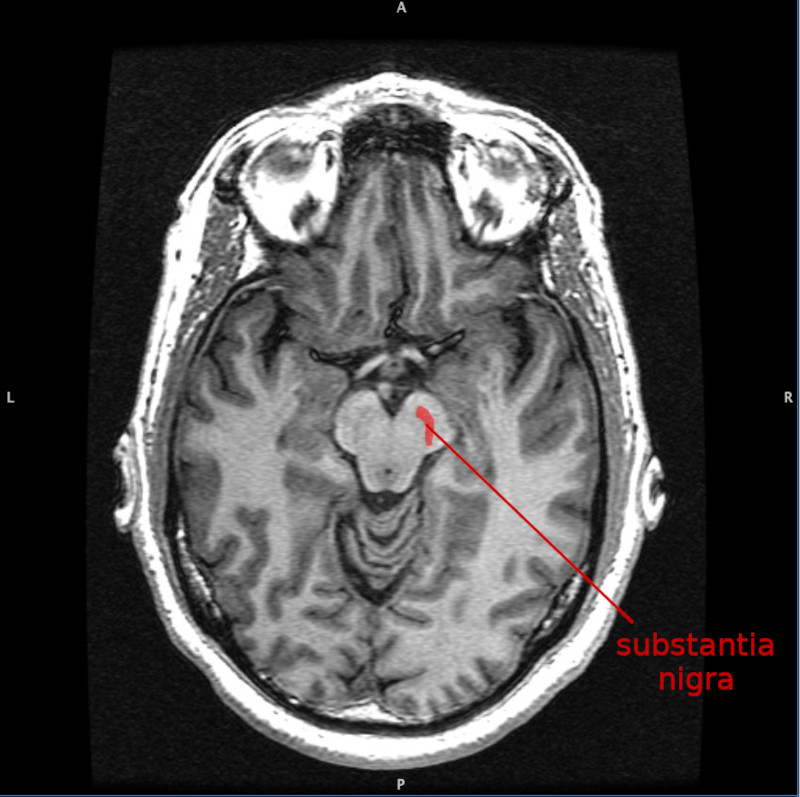

La morte delle cellule della substantia nigra, una regione mesencefalica, sembra essere all'origine del disturbo poiché esse compartecipano alla produzione della dopamina. Le ragioni per le quali le cellule muoiono sono di fatto sconosciute ed entrano in gioco i fattori di rischio, anche i più banali e onnipresenti come sostanze tossiche, traumi cranici e fattori genetici. Si è poi scoperto che chi fuma e beve caffè ha un minor rischio di contrarre la malattia!

La substantia nigra, insieme ad altri quattro nuclei, fa parte dei gangli basali, che si trovano nel mesencefalo, posteriormente ai peduncoli cerebrali. Sono strutture pari, una a destra ed una a sinistra.

La substantia nigra gioca un ruolo importante nel funzionamento cerebrale, con riferimento particolare al movimento degli occhi, alla pianificazione motoria, alla ricerca del piacere e della ricompensa, all'apprendimento ed alla dipendenza. Molti degli effetti generati dalla substantia nigra sono mediati dal Corpo striato (→).